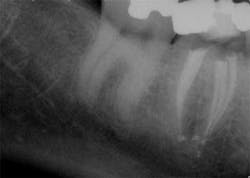

These are my least favorite teeth to treat. Most are heavily restored and the mesial-distal dimension is very small, resulting in no margin for error when locating the pulp chamber. Additionally, there can be significant inclination between the crown and root, and many will have two canals or branching at some level of the canal. (12,15) This lingual inclination of the root results in difficulty obtaining straight-line access into the buccal canal and makes locating the lingual canal almost impossible in some cases, especially if the lingual shelf of dentin is prominent. (Figure 2) Straight-line access into some lingual canals would need to be established through the mid-facial, and this is not a reasonable option for teeth restored with full-coverage crowns. (16)

have two canals. The second canal is lingual

to the main canal, and it is not uncommon for

the two canals to join at the apex. Tooth

No. 24 has a necrotic pulp and based on

the anatomy of teeth Nos. 23 and 26, a

second canal in tooth No. 24 should be expected.